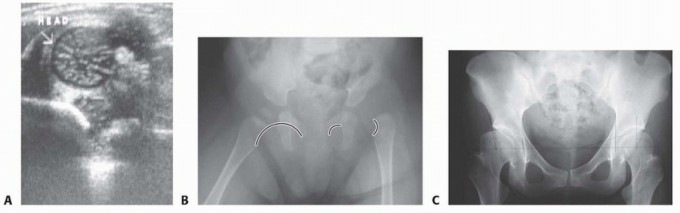

An absent or subluxated femoral head eventually leads to a flat, egg-shaped acetabulum, which is a consistent finding on three-dimensional computer modeling performed of the acetabulum (

FIG 2A

).

FIG 2 • A. Three-dimensional computer-generated hip model of adolescent with long-standing left hip developmental dysplasia. The acetabulum is shallow and elongated in its superior aspect, resembling an egg. B. Intraoperative left hip arthrogram of a dislocated femoral head (

FH

Arrowhead

shows the neolimbus (

NL

) contributing to blocking the reduction of the femoral head.

LT

, ligamentum teres.

With time, the neolimbus, which is abnormally formed articular cartilage, can develop at the edge of the acetabulum. It can be a barrier to reduction (

FIG 2B

*).8